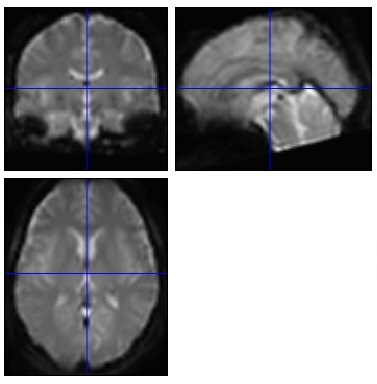

Normalisation

fMRIデータの前処理

PDF資料でNormalisationの方法を解説しています。